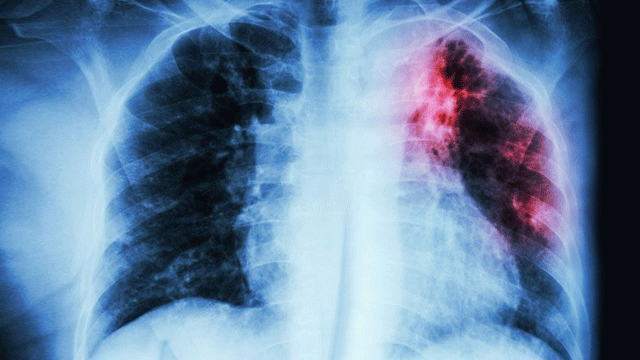

Tüberkülozun teşhisi kolay koyulamamaktadır. İlerlemesi sinsi olduğu gibi tetkiklerde de çok önemli bir bulgu vermeyebilmektedir. Tüberküloz olduğunu düşünülen bir hastaya önce sedimantasyon başta olmak üzere bir takım kan tetkikleri istenmektedir. Daha sonra akciğer grafisi ve akciğer tomografisi çekilmektedir. Fakat aslında tüberkülozun yüzde yüz teşhisini koyduran şey balgam da mikrop saptanmasıdır. Eğer hasta balgam çıkaramıyorsa ve diğer testlerle de sonuç alınamıyorsa bronkoskopiyle girilip hastalık düşünülen alanlardan örnekler alınmakta ve mikrop bu örneklerde aranmaktadır. PPD testi ise tüberküloz testi olarak bilinir ancak tüberküloz teşhisi konulmasını sağlamaz. Yalnızca kişinin tüberküloz mikrobuyla karşılaşıldığını göstermektedir. Ülkemiz koşullarında birçok insanda bu testin sonucu pozitiftir.

Tüberküloz solunum yoluyla alındığı için en sık akciğerlerde hastalık yapar, ama bunun dışında vücudun diğer bütün organlarında tüberküloz hastalığına yol açabilmektedir. Böbrek karaciğer, dalak, göz, beyin zarında yani bütün organlarda görülebilmektedir. Çocuklarda ise özellikle tüberküloz menenjitler şekline ortaya çıkmaktadır. Ayrıca mediasten adı verilen akciğer ve kalbin bulunduğu boşluk içerisindeki lenf bezlerini ya da bütün vücuttaki lenf bezlerini de tutabilmektedir. Boğaz bölgesine yerleşen Larenks tüberkülozu da hastalığın en sık bulaşan türlerindendir. Akciğer zarında sıvı toplaması, iltihap ya da yine akciğerde kavite de denilen yara şeklinde olabilmektedir.